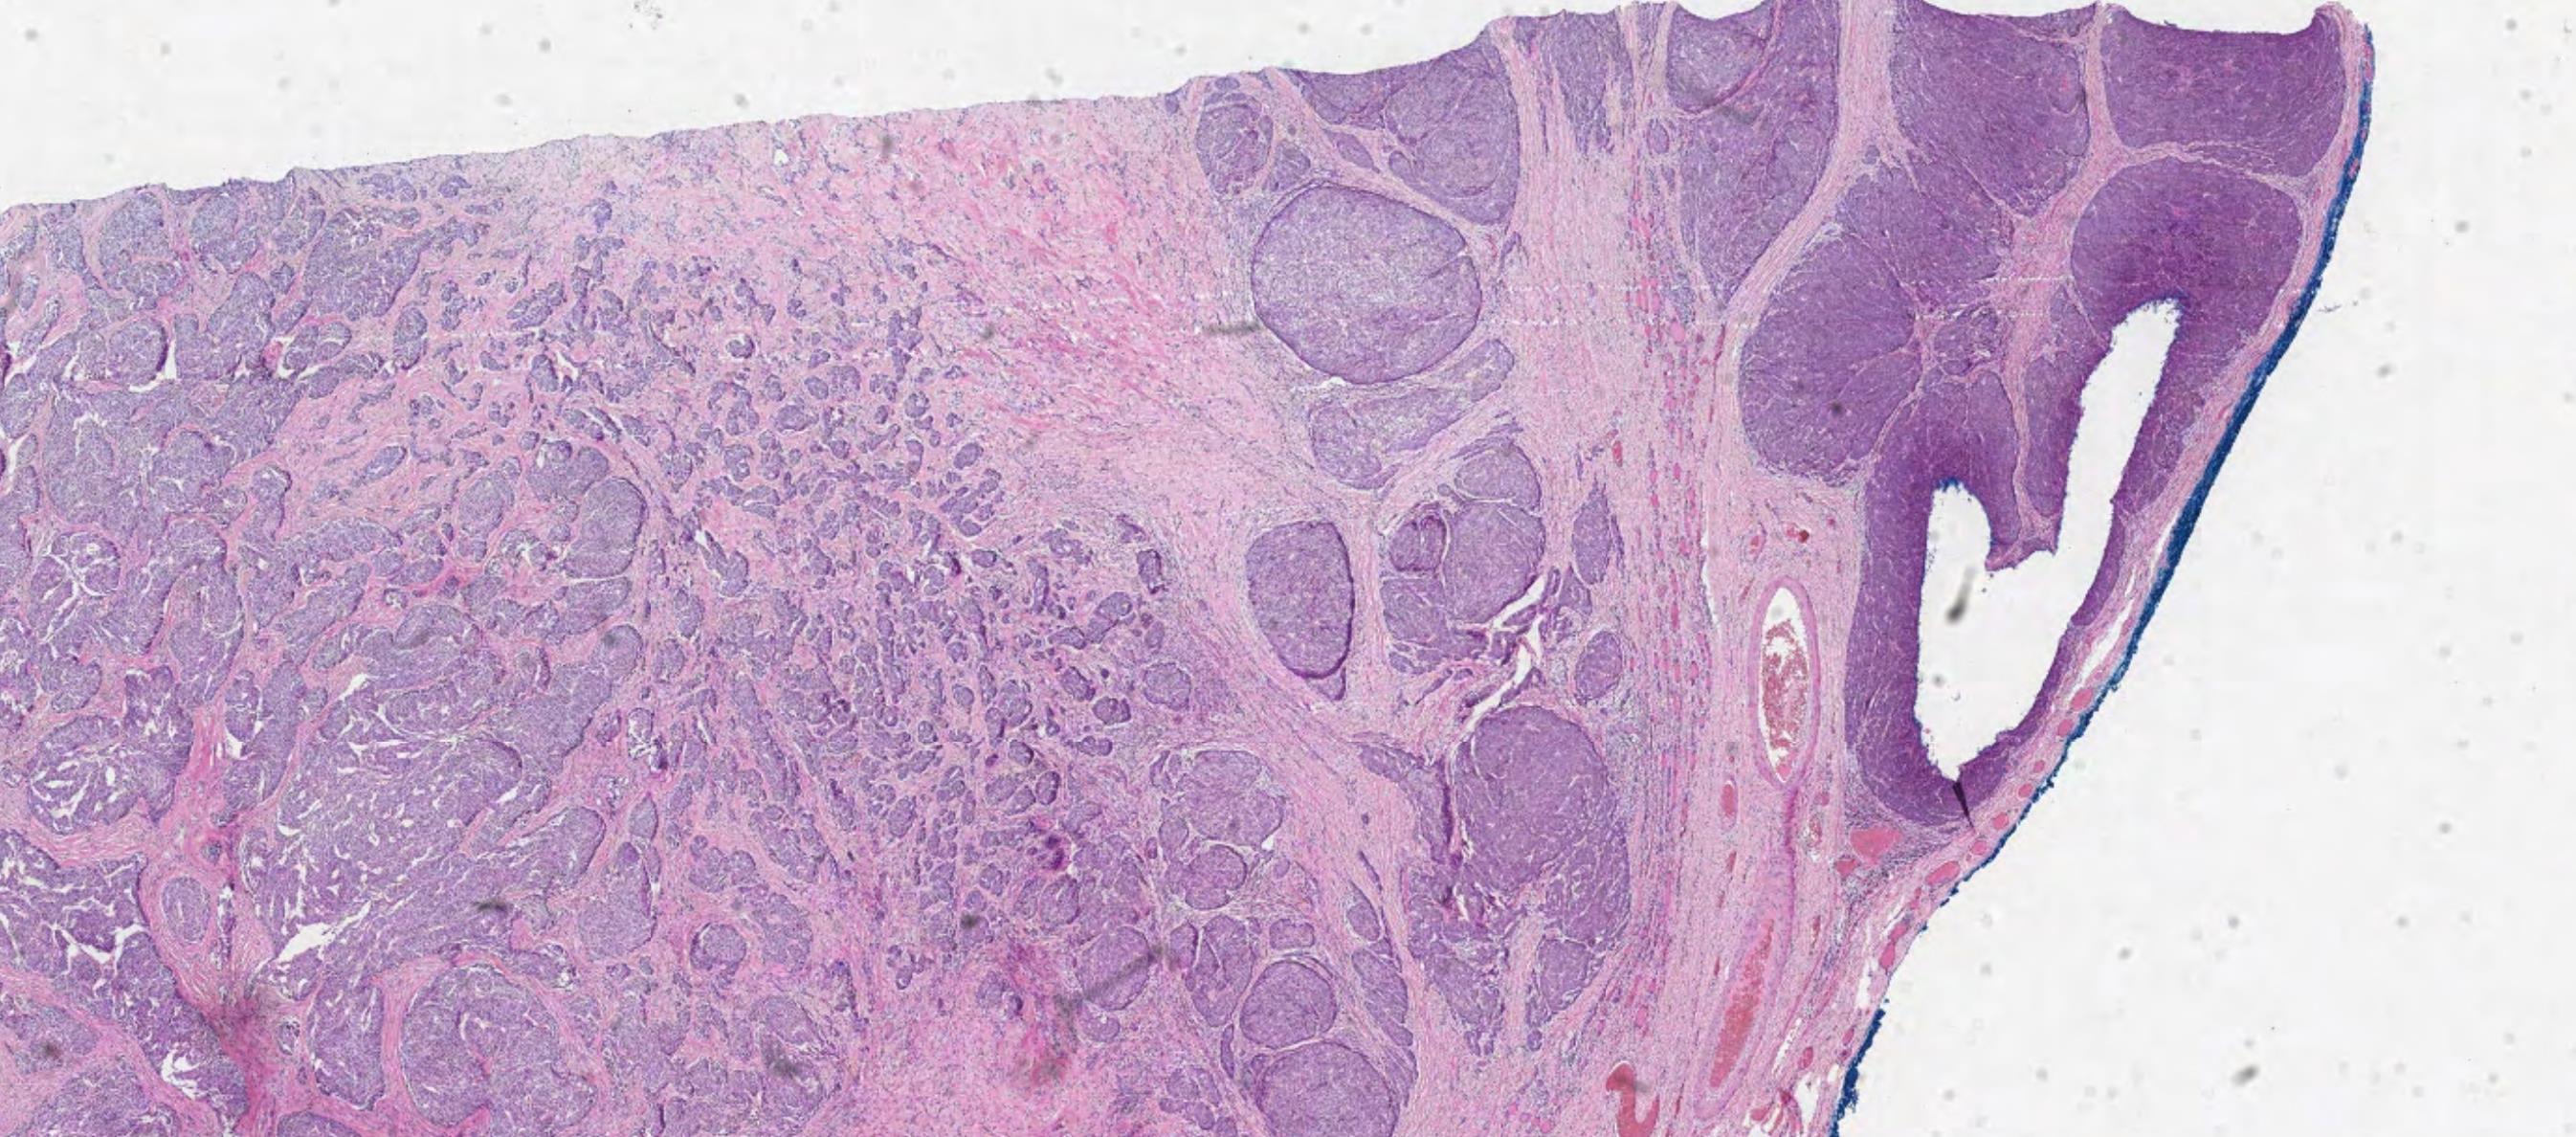

42-year-old Female, Left level 4 lymph node.

Case 4 Diagnosis

Metastatic diffuse sclerosing variant of papillary thyroid carcinoma

Diffuse enlargement, Solid tumour nests with squamous metaplasia, including squamous morules, dense sclerosis, numerous psammoma bodies, background chronic lymphocytic thyroiditis This tumour is common in children and young adults BRAF mutation (50%), RET/PTC1 rearrangement (28%), RET/PTC3 (14%) Highlights